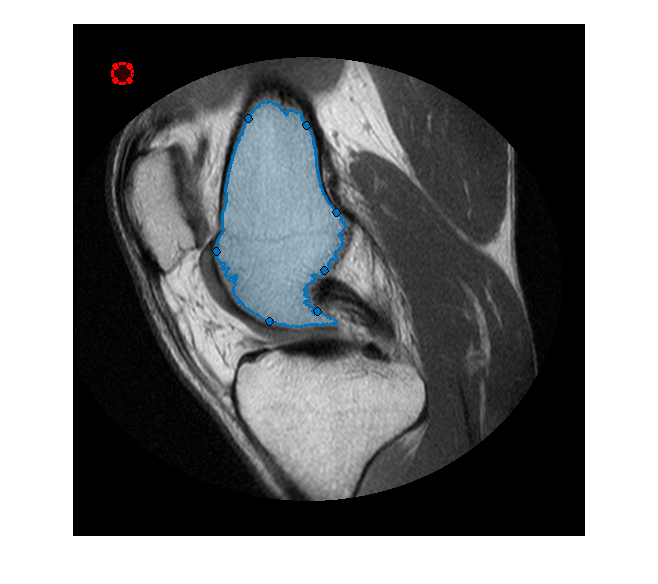

Создайте Круговой ROI, который будет использоваться в качестве средства стирания или инструмента редактирования ROI кисти. (Можно использовать любой images.roi.* классы путем создания небольшого изменения, упомянутого ниже).

he = images.roi.Circle(... 'Center', [50 50],... 'Radius', 10,... 'Parent', gca,... 'Color','r');

Сопоставьте два прослушивателя события с Круговым ROI. Каждый слушает для перемещения ROI, и другой слушает для того, когда перемещение останавливается. ROI, перемещающий функцию обратного вызова, пример убеждается, что имел свою привязку положения к пиксельным местоположениям и также изменил цвет (Красный/Зеленый), чтобы указать, удалит ли операция редактирования или добавит к целевому ROI от руки. Если ROI редактора прекращает перемещаться, мы создадим соответствующие бинарные маски для ROI редактора и целевого ROI от руки и сделаем необходимое редактирование. Наконец, мы преобразуем обновленную маску назад к объекту ROI от руки. Обеспечьте электричеством прослушиватель, чтобы реагировать каждый раз, когда этот ROI редактора перемещен

Эта анимация показывает добавление, и удалите операцию редактирования.

Это - ROI, перемещающий функцию обратного вызова. Эта функция гарантирует, что привязки ROI редактора к пиксельной сетке, и изменяют цвет ROI редактора, чтобы указать, добавит ли это к ROI от руки или удалять область от ROI от руки. Если центр ROI редактора вне целевого ROI от руки, удаляет операцию, в противном случае это 'добавит'.

Это - редактирование коллбэк ROI от руки, который добавляет или удаляет область ROI редактора, который пересекает целевой ROI от руки.

function editFreehand(hf, he) % Create a mask for the target freehand. tmask = hf.createMask(); [m, n,~] = size(tmask); % Include the boundary pixel locations boundaryInd = sub2ind([m,n], hf.Position(:,2), hf.Position(:,1)); tmask(boundaryInd) = true; % Create a mask from the editor ROI emask = he.createMask(); boundaryInd = sub2ind([m,n], he.Position(:,2), he.Position(:,1)); emask(boundaryInd) = true; % Check if center of the editor ROI is inside the target freehand. If you % use a different editor ROI, ensure to update center computation. center = he.Center; % isAdd = hf.inROI(center(1), center(2)); if isAdd % Add the editor mask to the freehand mask newMask = tmask|emask; else % Delete out the part of the freehand which intersects the editor newMask = tmask&~emask; end % Update the freehand ROI perimPos = bwboundaries(newMask, 'noholes'); hf.Position = [perimPos{1}(:,2), perimPos{1}(:,1)]; end